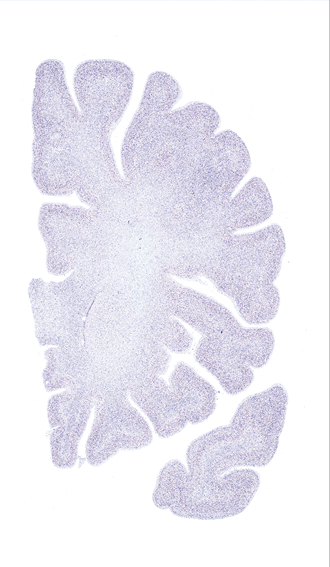

Hi-Resolution Sections · Cells (Nissl Staining) · Virtual Microscopy

Frontal sections (Nissl) from the Atlas Brain:

Slice ID:

r2-0571

Plate NR:

10

Position:

-19,1 mm